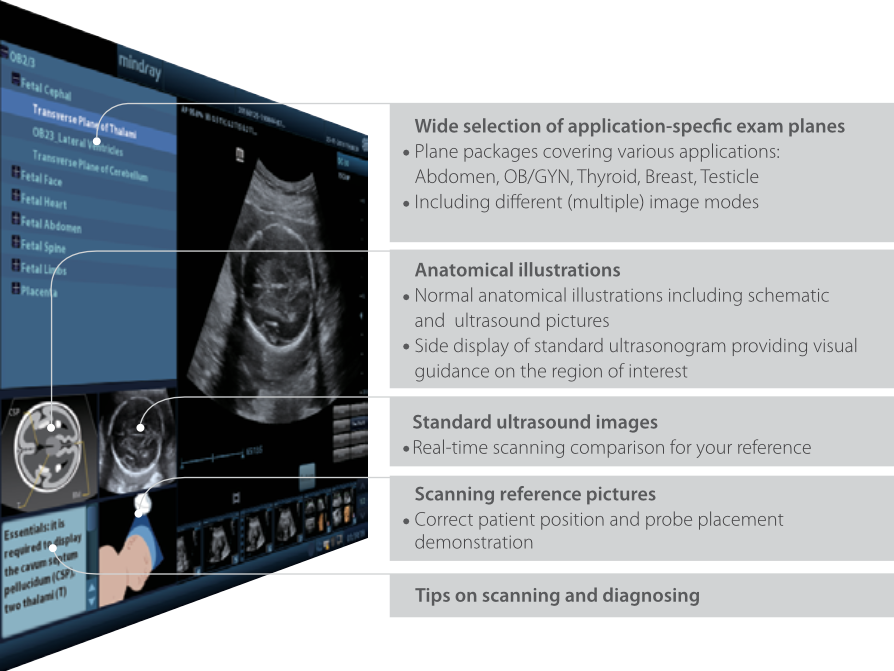

iScanHelper

Perangkat khusus sebagai panduan edukasi bawaan menghadirkan panduan bermanfaat kepada pengguna tentang 'bagaimana & apa' yang terkait dengan pemeriksaan ultrasound. iScanHelper mencakup ilustrasi anatomi, gambar ultrasound standar, gambar rujukan scanning, dan cara melakukan pemindaian dengan baik.